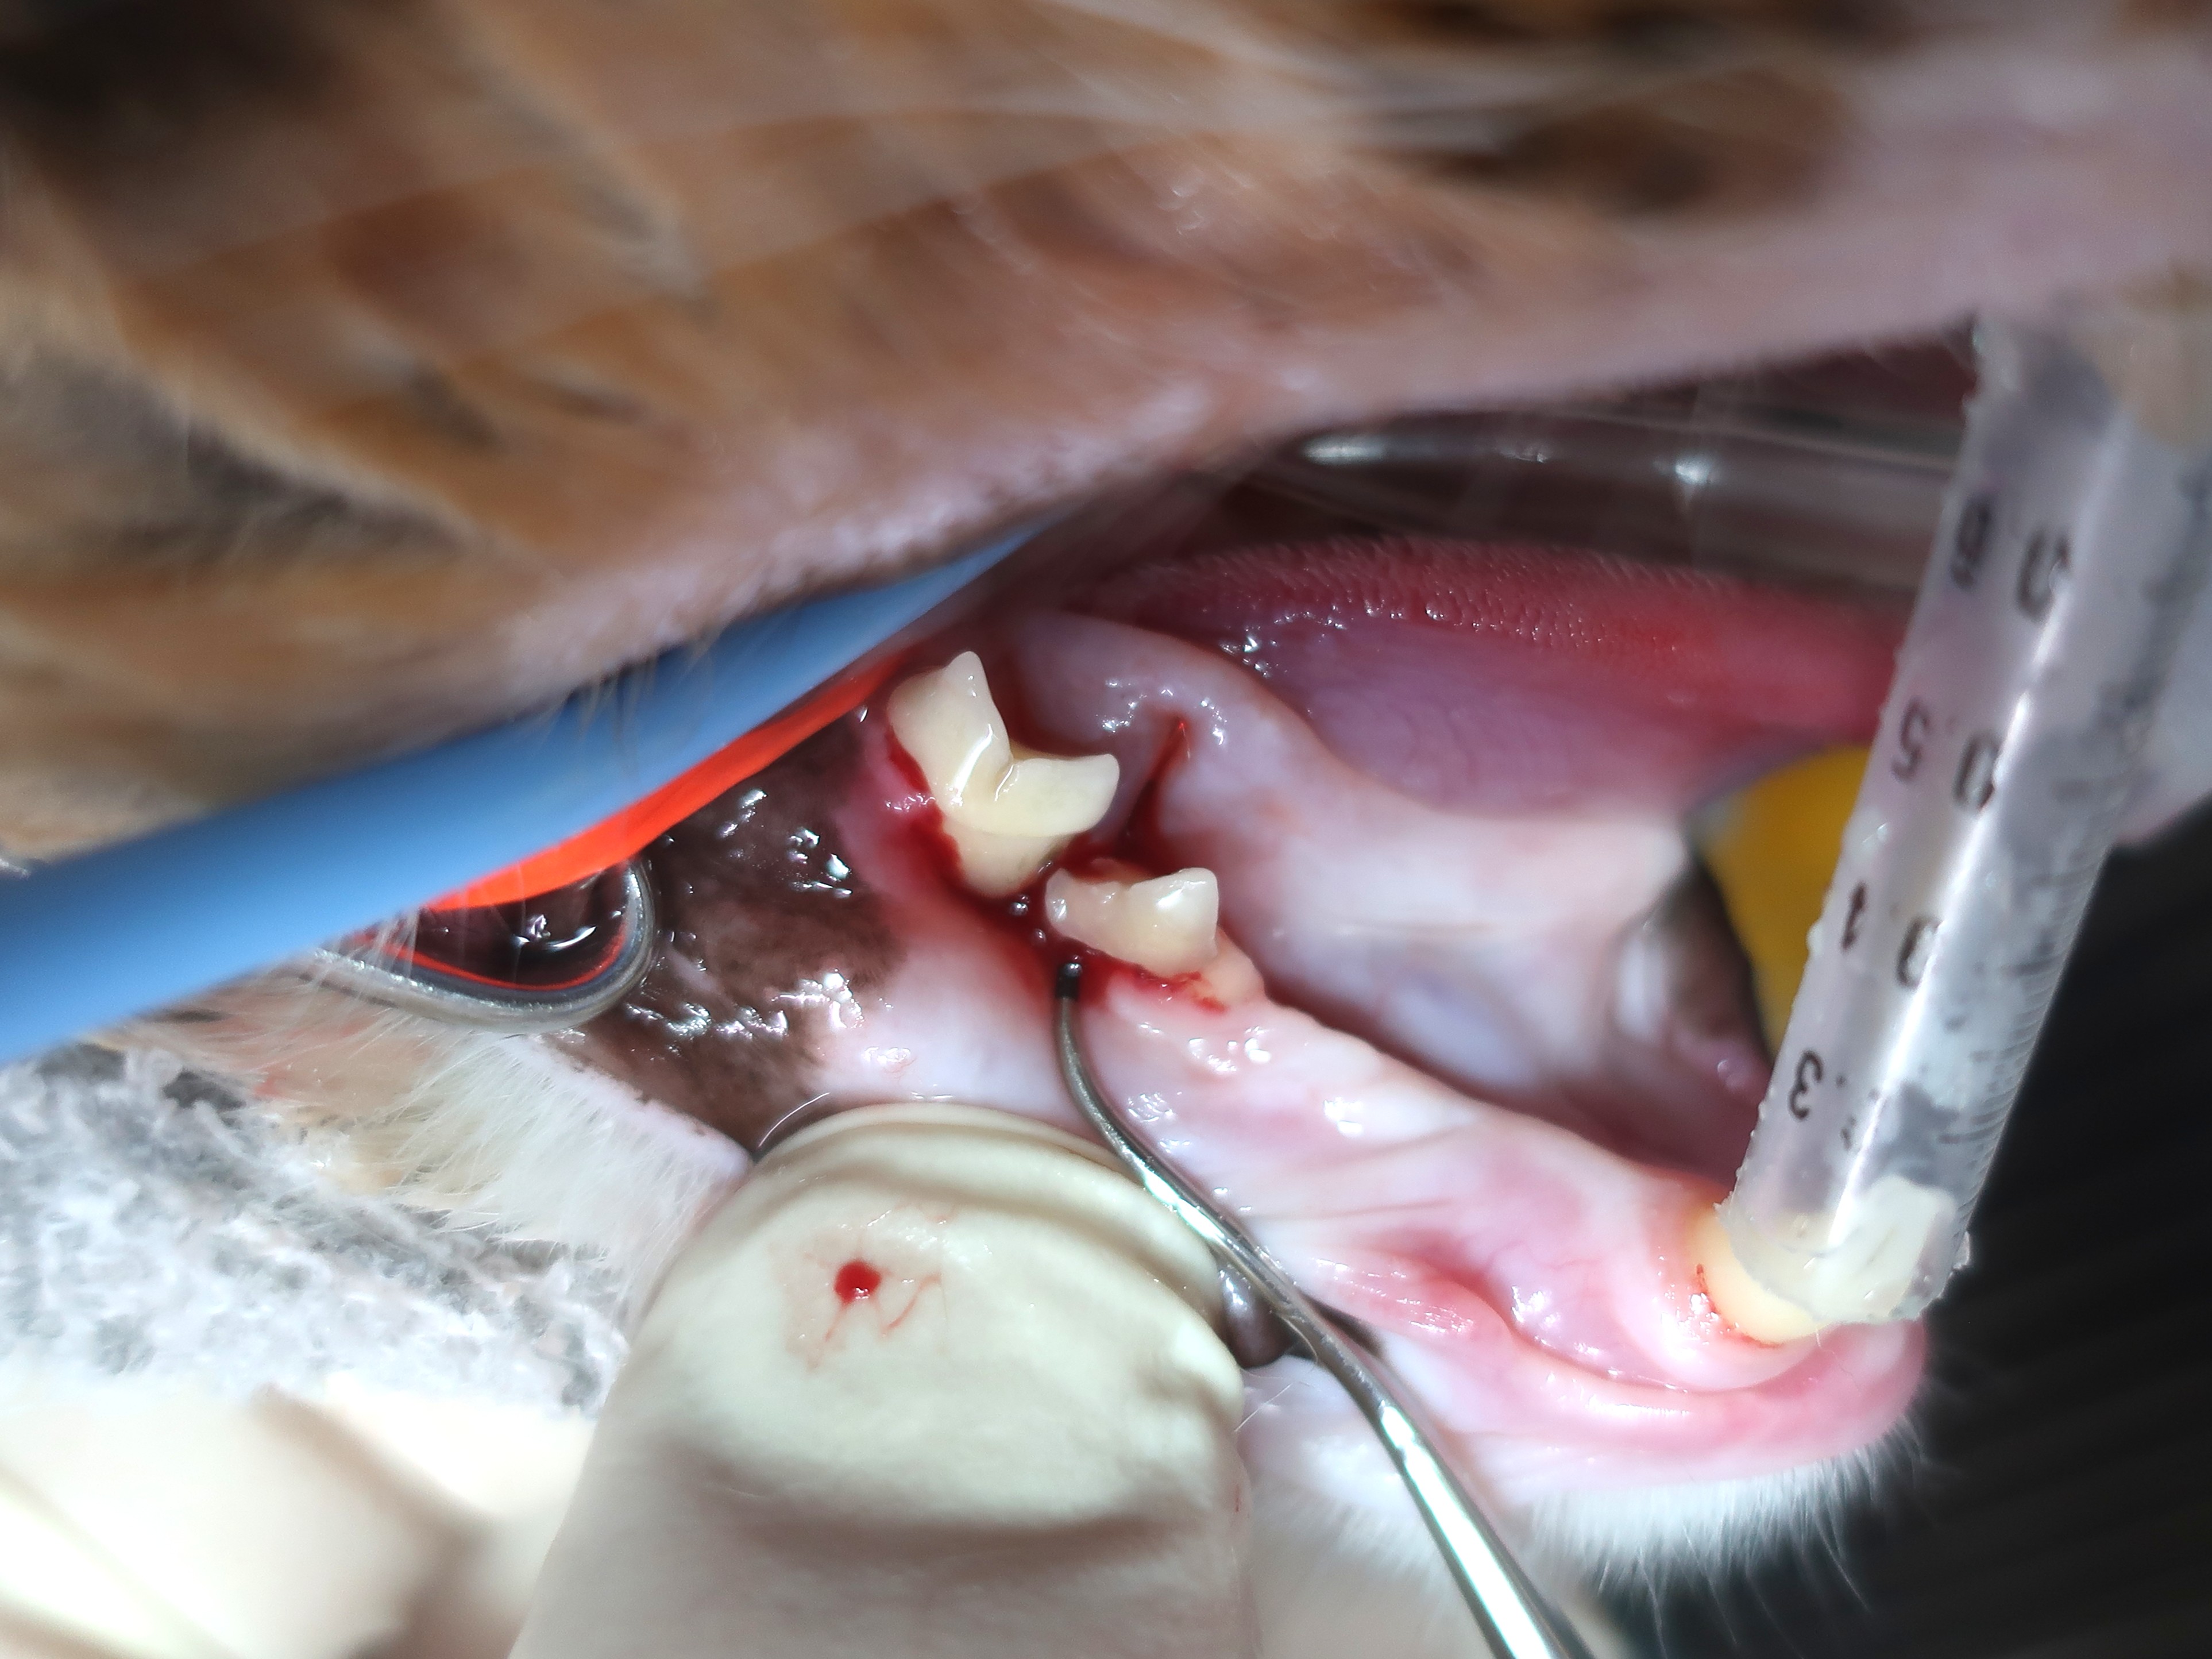

歯周プローブ検査

歯周ポケットの深さを測ります。

右下顎第2前臼歯・第1後臼歯のポケットがもっとも深く、4~5mm。

少し触ると出血する状態でした。(写真1枚目)

根分岐部病変(歯周病が進み歯槽骨が溶けてしまい歯根部が露出している状態)も起こっており、

プローブが外側から内側へ貫通しています。(写真2枚目)

歯のぐらつきもありました。